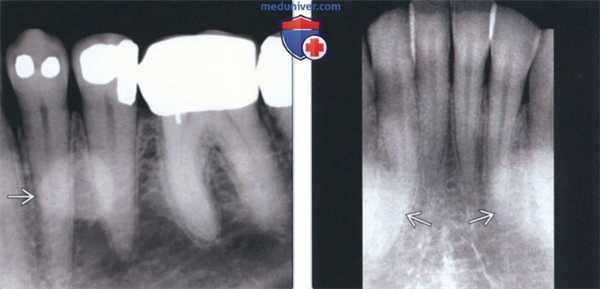

(Слева) На периапикальной рентгенограмме области средней трети корней премоляров слева определяется четко отграниченный рентгеноконтрастный участок. Такая локализация типична для нижнечелюстных валиков, хотя валики большого размера могут распространяться кзади к молярам и кпереди к резцам. Обратите внимание на отсутствие просветления на периферии. Четкие и ровные края помогают отличить валик от идиопатического остеосклероза.

(Справа) На периапикальной рентгенограмме центральных резцов нижней челюсти определяются типично выглядящие двухсторонние нижнечелюстные валики.